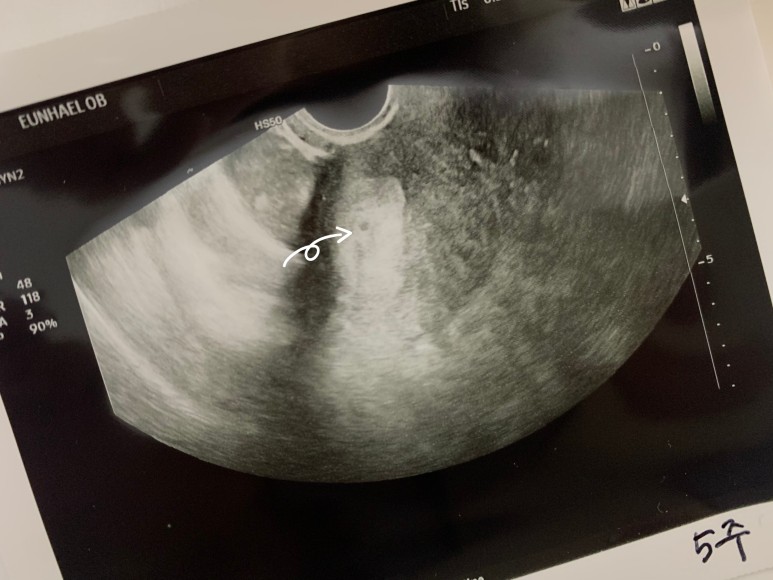

마지막 생리 예정일 날짜를 확인하고 자궁경부암 검진할때 앉아봤던 그 일명 굴욕의자(!)에 어정쩡하게 다리를 벌리고 앉았다. 나는 배란테스트를 해서 배란일도 정확히 알고 있었는데, 배란일 날짜도 말씀드리니 그건 별로 신경쓰시지 않았다. 요리조리 꼼꼼히 살피었는데 내가 인터넷에서 봤던 까맣고 동그란 아기집이라고 하는 건 당최 보이질 않았다. 읭..? 의사선생님께서 샅샅이 살펴보다 겨우겨우 찾아낸, 이제 막 동그라미가 되려고 하는, 뿌연 안개같은 것에 쌓여있는 까만 점이 이제 아기집이 될 것(?)같다고 하셨다. 하지만 아직 확실히 아기집을 본 것은 아니라 임신이라고 확정짓긴 어렵고, 추가로 피검사를 해서 임신 수치를 확인해봐야 할 것 같다고.